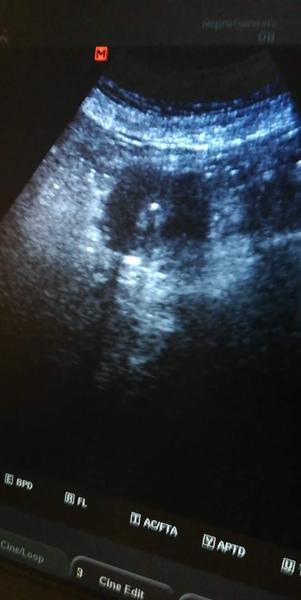

@sadovka Ahojky ja chodim do Reprogenesis v Brne.Vcera mi odebrali 21vajicek,15zralych a dnes je 13embryi.V nedeli jdu na ET